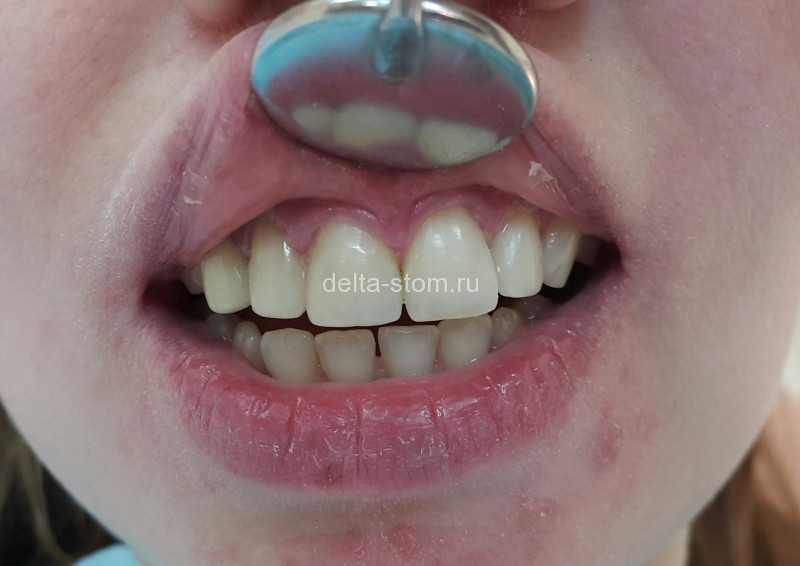

Установка керамических виниров

К нам обратилась пациентка с давней мечтой - сделать улыбку белоснежной. Основное пожелание – максимально светлый оттенок будущих реставраций. И вот результат.

Что мы сделали:

- Провели фотопротокол, цифровую диагностику сканером 3shape,

- Составили план лечения,

- Изготовили и установили 20 безупречных керамических реставраций оттенка Bleach 2!